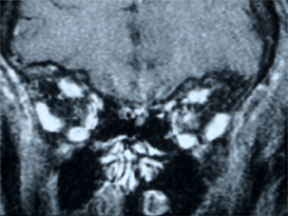

• MRI检查

MRI结果

• 左眼视神经增强伴颅内蔓延,病损累及第二视神经 (3, 4 5)

• 符合视神经脑膜瘤的表现

• 肿瘤可能起源于眶内的视神经鞘膜在颅内孔处,向颅内生长